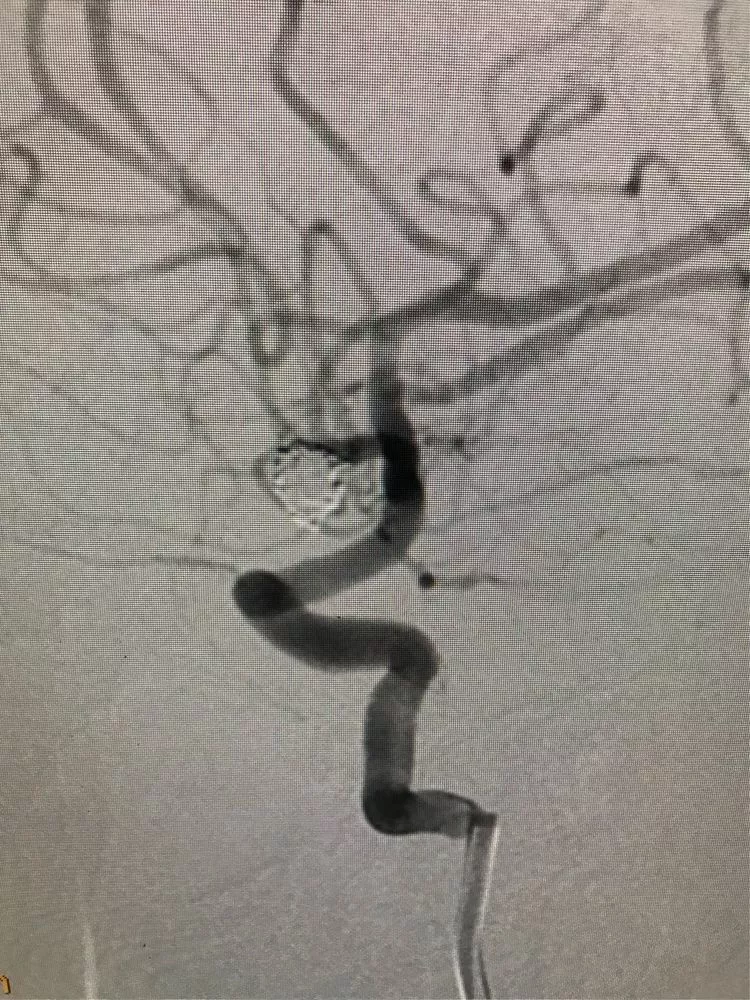

最后的影像。(瘤颈与前交通的切线位,没有弹簧圈突入前交通。)

正位,看双侧大脑前A2。

侧位。